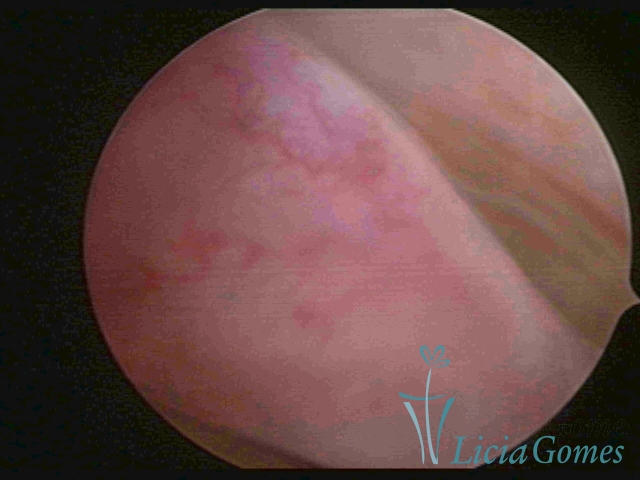

ENDOCERVICAL POLYPS

Benign tumors resulting from the reactive focal proliferation to inflammatory processes or hyperestrogenism situations, which may be sessile (with a large implantation) or stalked.